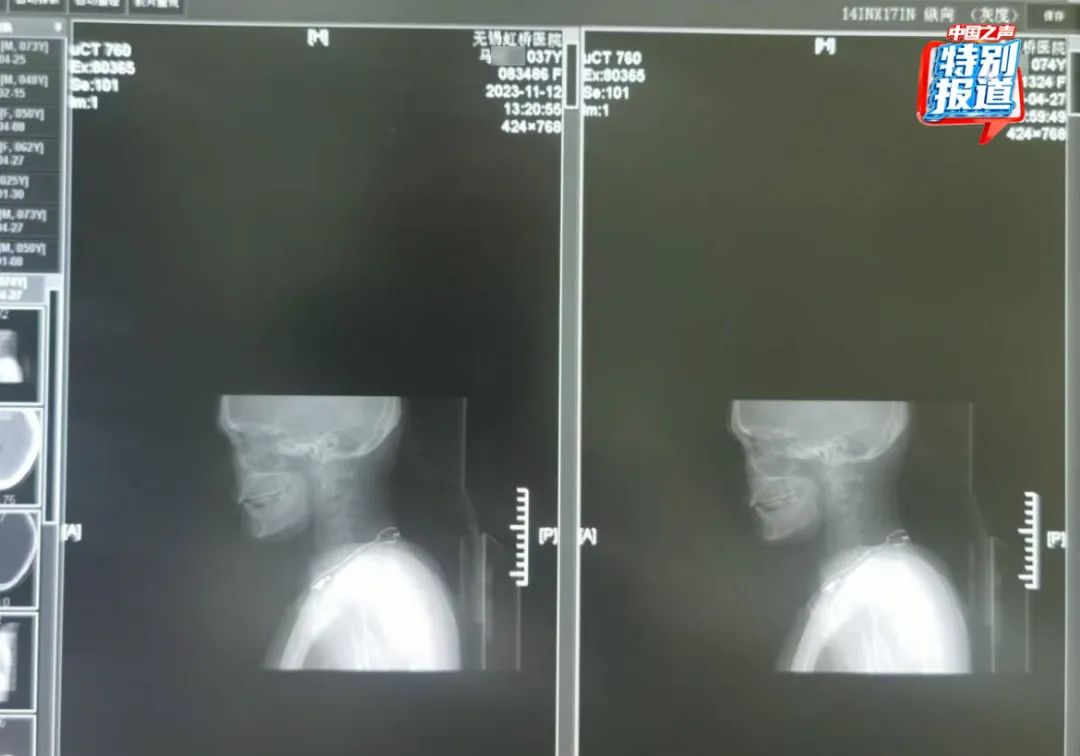

74岁的患者莫某在2023年4月27日拍摄了胸部和颈椎的CT,她的片子看起来和实际患者37岁的马某某在2023年11月拍的片子高度相似,片子里能直观看到项链都一模一样。